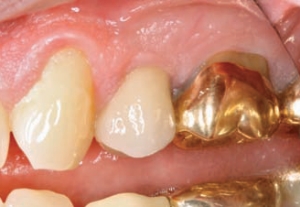

Figures 10 & 11--Deteriorating crown and Cerec 3D restoration

In most publications the excitement and interest seems to revolve around anterior aesthetics. Which anterior material and technique seems to look the best and last the longest? With so much focus on veneers and other anterior aesthetics, sometimes the posterior aspect of the mouth seems to be overlooked. In reality, posterior restorations are the “bread … Read more